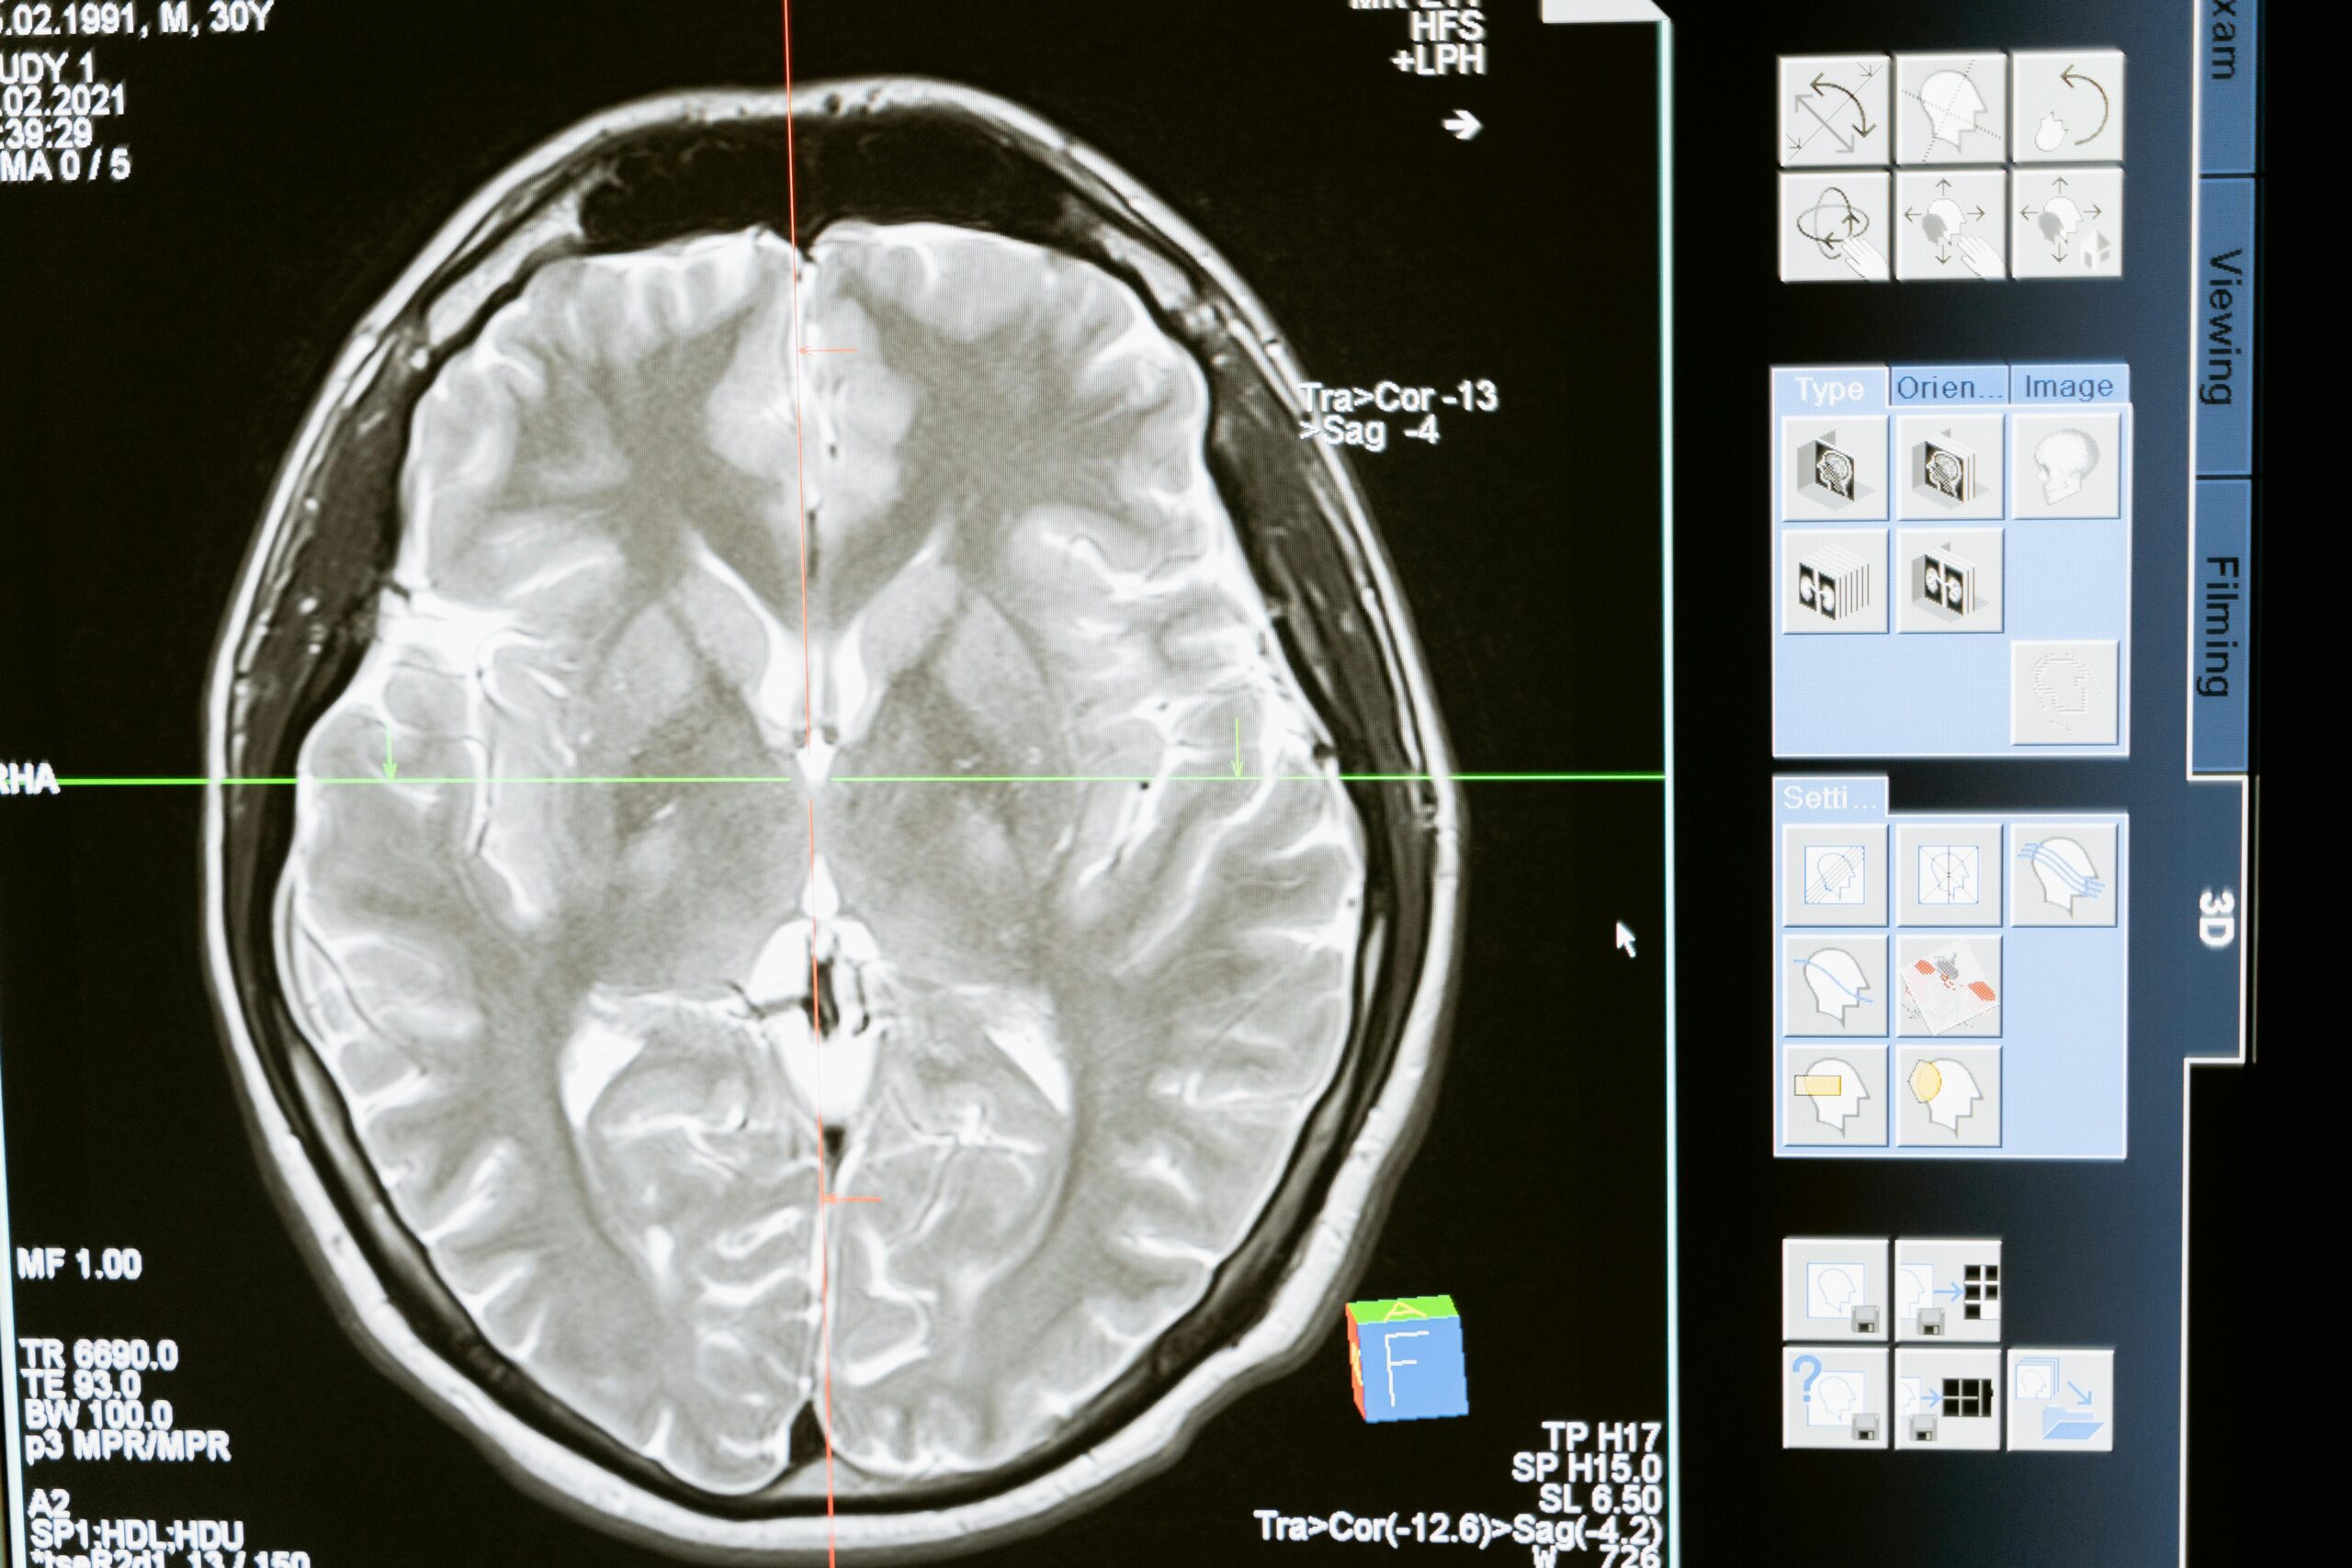

Doctors begin with your medical history and physical exam. They ask about symptoms, injury history and family patterns. They check reflexes, memory and brain function. Tests like EEG and MRI look for abnormal electrical activity in the brain or structural problems.

The EEG reads signals to capture hidden seizure patterns. Imaging tests show tumors, scars or infections. Sometimes doctors use video monitoring to watch episodes. These steps remove confusion between fainting, panic attacks or sleep disorders. Early diagnosis helps build stronger treatment plans.